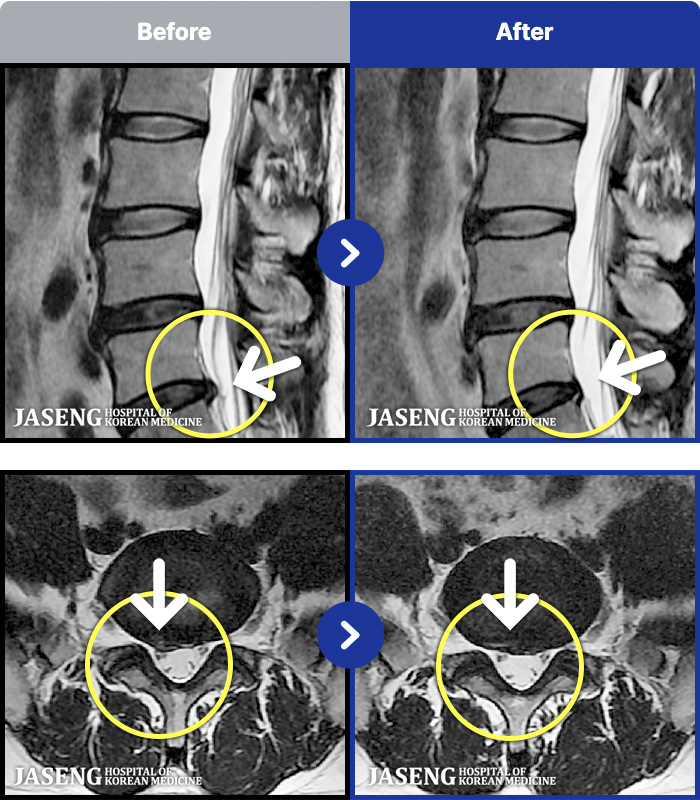

MRI ġ

MRI ũ ʸ Ȯϼ.